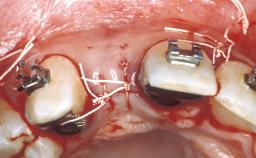

In September 2004, a 38-year-old female patient, a nonsmoker, was referred to our clinic for the replacement of the missing left central maxillary incisor (tooth 21),which had been removed two months before the initial appointment due to a vertical root fracture. The dental patient history revealed that the tooth in question had supported a ceramo-metal crown for more than ten years before the root fracture occurred. Implant therapy (single-tooth replacement) was considered the first therapeutic choice, as the neighboring teeth did not require significant restoration. The patient was in good general health, and her medical history revealed no significant findings.